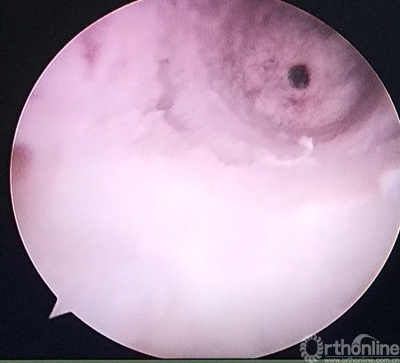

重建后关节镜检查见ACL的走向及张力等均好。

关节镜从前内入路进入,清晰的见到原胫骨隧道内口与返修后的相距较远。